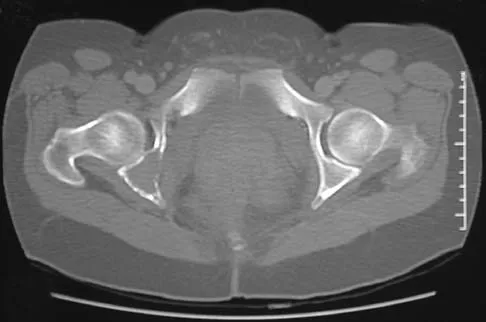

The mother of a 26-month-old boy reports that he has been unwilling to bear weight on his left lower extremity since he awoke this morning. She denies any history of trauma. He has a temperature of 99.4 degrees F (37.4 degrees C), and examination reveals that abduction of the left hip is limited to 30 degrees. Laboratory studies show a WBC of 11,000/mm3 and an erythrocyte sedimentation rate of 22 mm/h. A radiograph of the pelvis is shown in Figure 13. Management should consist of

Explanation

The most likely diagnosis is transient synovitis. Initial management should consist of bed rest and serial observation to rule out atypical septic arthritis of the hip. In an unreliable family situation, hospitalization for bed rest and observation may be indicated. Other disorders such as proximal femoral osteomyelitis, leukemia, juvenile rheumatoid arthritis, pelvic osteomyelitis, diskitis, and arthralgia secondary to other inflammatory disorders should be considered. However, these disorders are unlikely because of the paucity of abnormal clinical signs exhibited by the patient. On the other hand, transient synovitis of the hip in children is a diagnosis of exclusion; other possibilities should be explored if the patient's symptoms do not follow a typical course and resolve in 4 to 21 days.